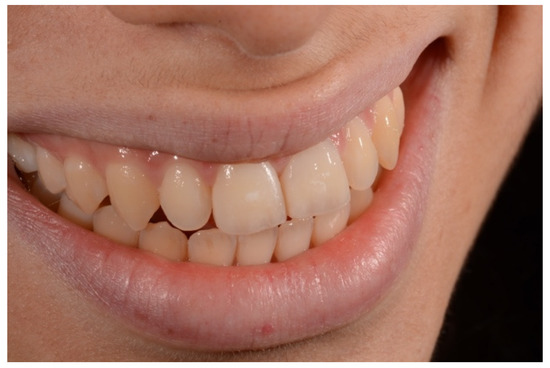

2. Case Presentation